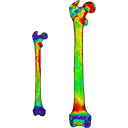

Tutorial 07: thickness within objects and scalar normalization

Difficulty:

Description

Tutorial 07 includes: More infos |

2 files: Tutorial_instructions Tutorial_data |

Tutorial 08: thickness between objects

Difficulty:

Description

Tutorial 08 includes: More infos |

2 files: Tutorial_instructions Tutorial_data |